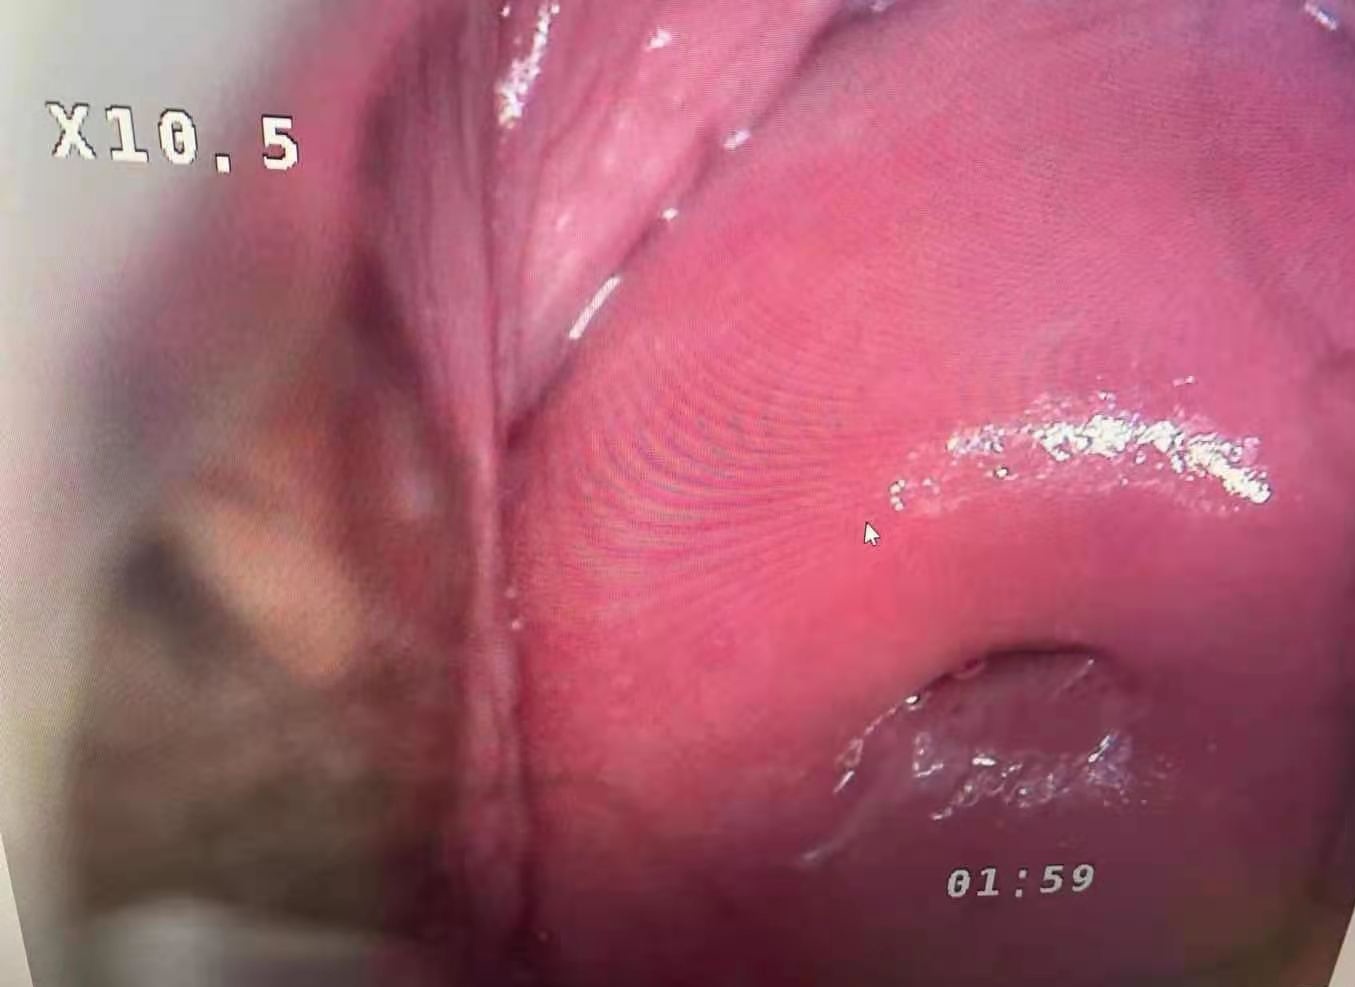

**Extra long depth of field, super large field of view, super three-dimensional sense, realistic color reproduction, unique light path design, providing true 3D visual effects for pre-cancerous, pre-lesional punctiform vessels, columnar epithelium and some tiny lesions .

**50times System Magnification ,17 times optical amplication,3 times Digital amplification.able to output divine clear view of the examination lesion parts. Provide doctors with 3D visual image of the epithelial tissues,and different levels of the blood vessels. **LED light source,lifespan more than 20,000hours. **Horizontal Resolution up to 2064.

Real cervical diagnosis pictures